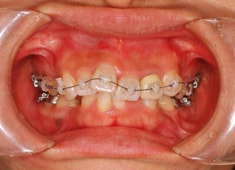

治療後(3年2ヶ月後)